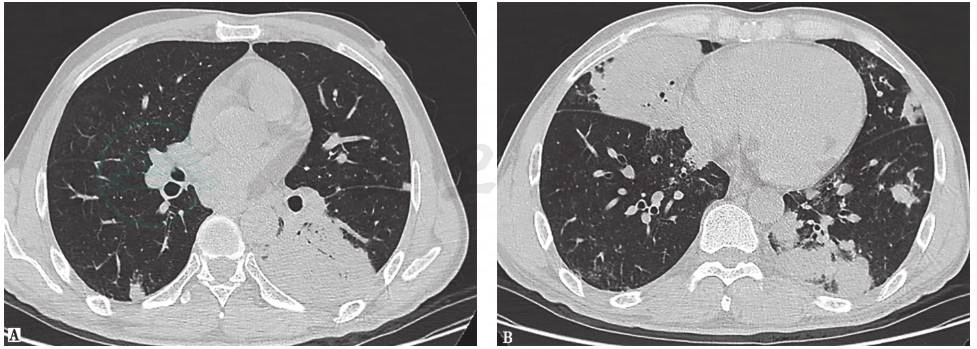

病毒性肺炎:严重急性呼吸道综合征(severe acute respiratory syndrome,SARS)、中东呼吸综合征(middle east respiratory syndrome,MERS)或H1N1等流感病毒(图1)所致的病毒性肺炎,常发病急骤,胸部影像学表现主要为间质性病变,可在数天内进展为“白肺”。腺病毒所致的病毒性肺炎可出现肺实变表现,该病多发生于儿童,但也有成年人发病的报道,除累及肺部以外,还可累及肝、肾、血液系统等,其病程有自限性。本例患者的临床表现与上述情况不符,可检测呼吸道病原协助鉴别。

图1 H1N1感染胸部影像学表现

胸部CT可见双肺多发小斑片磨玻璃实变影

图2 肺曲霉菌病胸部影像学表现

胸部CT可见右上肺肿块样高密度影,伴支气管充气征